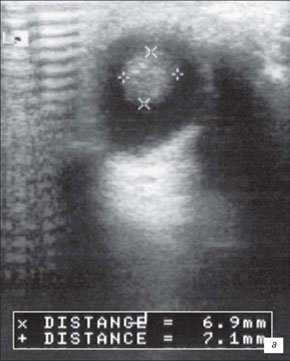

Ультразвуковое В-сканирование. Крупные, кальцифированные опухоли проявляются как отдельные, овальные, солидные массы с чёткой передней границей.

а) Небольшая ретинобластома. В ткани опухоли видны более плотные мелкие структуры (включения кальция).